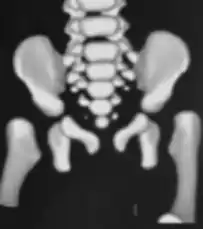

MRI- bilateral dislocation of hips, epiphyseal core (small arrow), and dysplastic acetabulum (large arrow)

CT hips